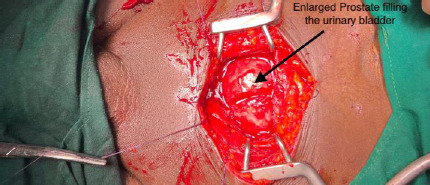

Giant prostate hyperplasia is defined as prostate hyperplasia with a weight greater than 500 grams. This condition is rare. We present the management of a case of giant prostate hyperplasia (541 grams on CT scan) with a surgical enucleated volume of 800 grams in a patient who presented with haematuria. An abdominal-pelvic CT scan was required to differentiate it from a suspected bladder tumour. This case was successfully managed with a favourable outcome following open transvesical prostatectomy, ensuring minimal blood loss. This case report and review provide an update on the management of giant prostate hyperplasia, with emphasis on the prevention and management of haemorrhage.